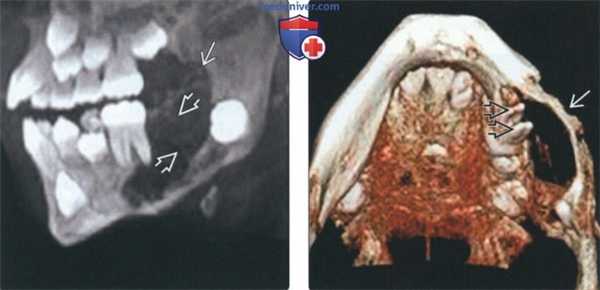

(Слева) На КЛКТ (вид сбоку) у этою же пациента определяется поражение венечного отростка. Обратите внимание на тонкую перегородку в образовании.

(Справа) На трехмерной реконструкции (КЛКТ) у этого же пациента визуализируется АФ (вид снизу). Обратите внимание на вздутие щечной кортикальной пластинки в образовании отчетливо видны мезиальный и дистальный корень первою моляра. Нижний край нижней челюсти сохранен.